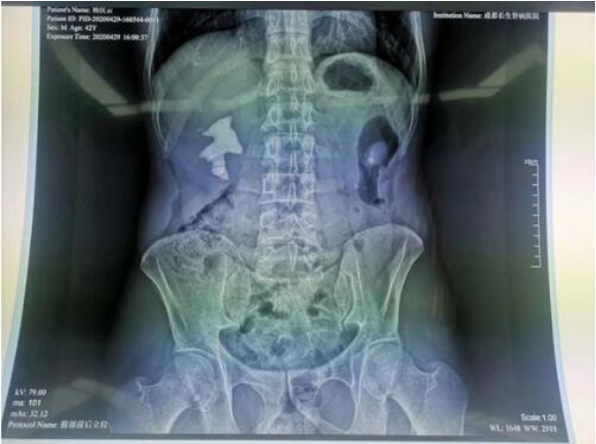

经诊断,杨先生双侧肾都有结石,左侧的结石直径1厘米左右,暂时不对肾功能造成影响,可不予处理;右侧是一个巨大的填满性铸型结石,直径5.0cm*4.5cm。右侧结石已经充满肾脏空间,如果不尽快取出,会进一步引发梗阻而造成肾功能破坏,也会因长期刺激肾脏而有癌变风险。

要顺利完成杨先生的取石手术,要突破这样几个难点:1、结石充满肾脏,没有缝隙,建立通道难度极大;2、患者曾在同一部位做过相同手术,人体正常组织解剖可能发生改变,有粘连可能,增加了术中出血风险;3、患者肾脏积水不严重,对穿刺要求非常高,技术不成熟可能造成穿刺失败,手术无法进行;3、患者结石大,手术时间长,无法通过一次手术将结石完全清除干净,且有可能需要多通道穿刺。

5月1日,患者经充分完善的术前准备后,手术顺利开展。一期手术进行50分钟后,右肾结石清除约三分之一,考虑剩余结石仍较多,继续手术,杨先生身体可能无法承受,郭振新主任决定终止手术,5天后行二期手术。5月7日二期手术如期进行,利用一期手术的通道,不出血,几乎没损伤,40分钟后,杨先生右肾结石完全清除。术后检查无残余结石,无梗阻,肾脏排泄正常。手术不留引流管,做到了无管化。